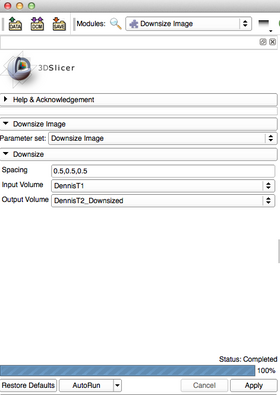

- Input Parameters:

- Size [-s --spacing] : The value of each voxel resolution for 3 dimensions

- Input Volume [index: 0] : Input volume to be resampled.

- Output:

- Output Volume [index: 1] : Resampled Output Volume